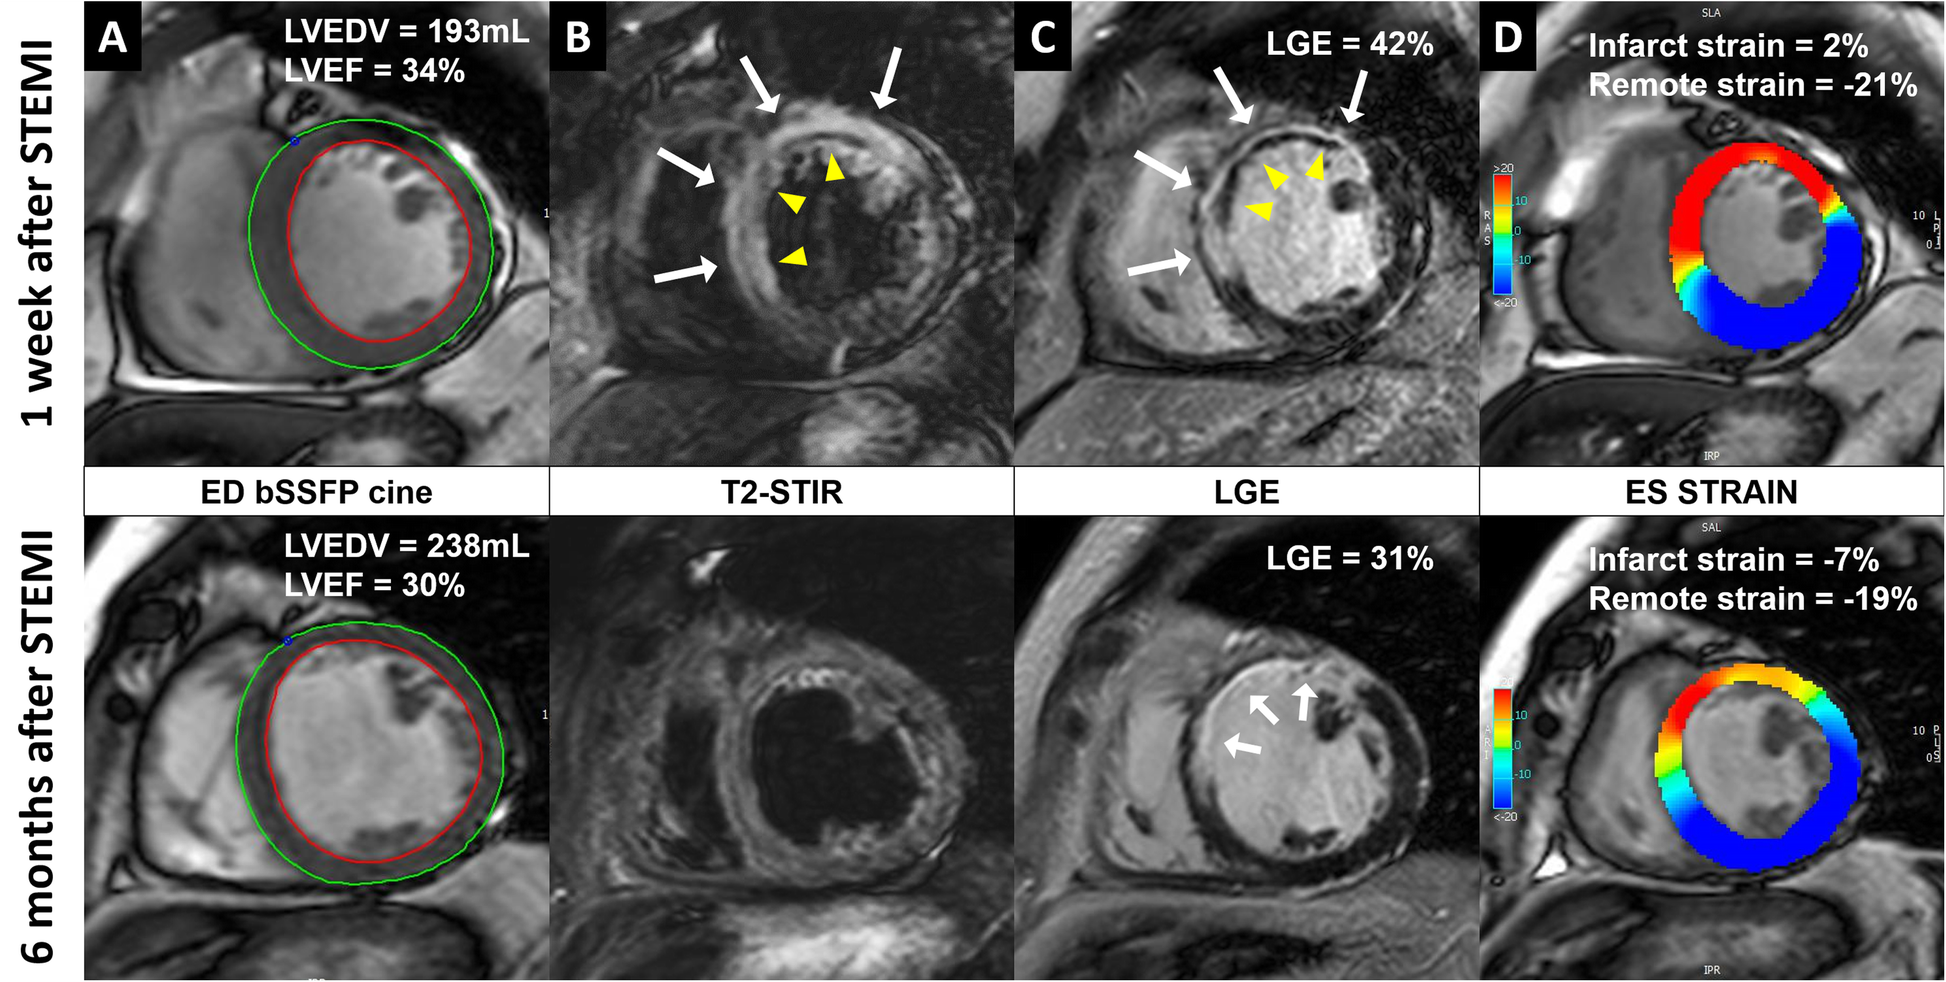

Fig. 3

A patient with a proximal LAD infarct receiving standard STEMI treatment. a, balanced steady state free precession (bSSFP) end-diastolic images with endo- and epi-cardial contours. The patient developed adverse left ventricular (LV) remodeling (defined as ≥ 20% increase in LV end-diastolic volume (LVEDV) and had a slight reduction in LV ejection fraction (LVEF) at 6 months after STEMI. b, T2-weighted short tau inversion recovery (STIR) images, showing the presence of edema (white arrows) and intramyocardial hemorrhage (IMH) (yellow arrowheads) at 1-week after STEMI. c, late gadolinium enhancement (LGE) images, showing the presence of acute ischemic injury (white arrows) with microvascular obstruction (MVO, yellow arrowheads) at 1 week after STEMI and infarct scar (white arrows) at 6-months. d, end-systolic bSSFP images with feature-tracking circumferential LV strain overlay. At 6 months the infarct zone circumferential strain improved despite the presence of a huge infarct with IMH and MVO in the acute phase, while the remote zone strain slightly declined bSSFP, balanced steady state free precession; ED, end-diastolic; ES, end-systolic; IMH, intramyocardial hemorrhage; LAD, left anterior descending coronary artery, LGE, late gadolinium enhancement; LV, left ventricular; LVEDV, left ventricular end-diastolic volume; LVEF, left ventricular ejection fraction; MVO, microvascular obstruction; SSFP, steady-state free precession; STEMI, ST-segment elevation myocardial infarction; STIR, short tau inversion recovery.